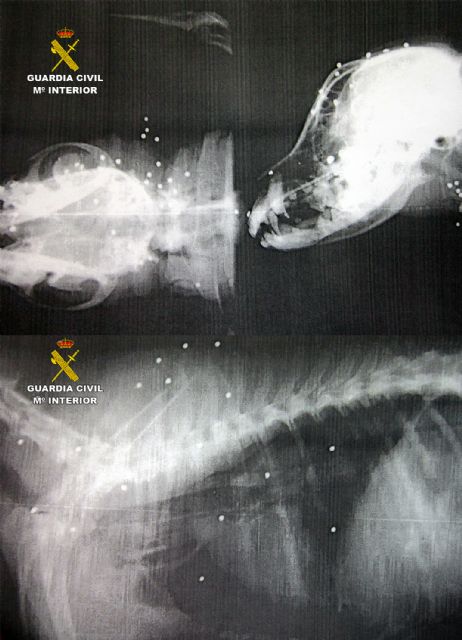

Uno de los canes recibió el impacto de 58 perdigones que le causaron lesiones graves y la pérdida de un ojo

Uno de los canes tuvo que ser atendido en un hospital veterinario de Murcia, donde quedó ingresado debido a la gravedad de las heridas causadas por el impacto de 58 perdigones pequeños proyectiles de plomo con forma redondeada que contienen los cartuchos. Los proyectiles le provocaron múltiples heridas y la pérdida de visión en uno de sus ojos. El otro perro alcanzado por un disparo, un cachorro de unos meses, presentaba heridas en el hocico, pero de carácter menos grave que el anterior.

Se adjuntan imágenes de las radiografías efectuadas al perro más afectado donde se aprecian los perdigones de plomo en el interior de su cuerpo.